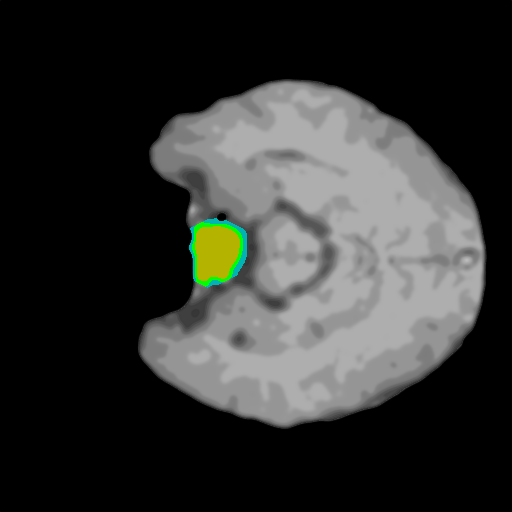

Extensive experiments have been performed in the current setup, and experimental outcomes are reported with the demonstration of numerical and statistical analyses using the proposed QFS-Net, QIS-Net [39], convolutional U-Net [18] and Residual U-Net (URes-Net) architectures [20]. The human expert segmented skull-tripped contrast enhanced DSC brain MR input image slices of size and ROIs are provided in Figure 5 as samples. The demonstration of QFS-Net segmented images followed by the essential post-processed outcome on the slice no. for class level with four distinct activation schemes () are shown in Figure 6. It is evident from the experimental data provided in Table LABEL:tab1 that the proposed QFS-Net performs optimally for the -connected quantum fuzzy pixel information heterogeneity assisted activation () with and gray scale set in comparison with other thresholding schemes and gray scale sets under the four evaluation parameters () [44]. The segmented tumors obtained using the proposed self-supervised procedure under class transition levels with four different thresholding schemes , , and are demonstrated in Figures 7- 8 for the class boundary sets and [39], respectively. The segmented images using the remaining two class boundary sets ( and ) [39] are provided in the supplementary materials section. The segmented ROIs describing the whole tumor region after the masking procedure using QIS-Net, U-Net and URes-Net are also reported in Figure 9.